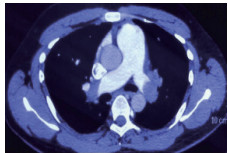

例2 72岁,男性。主因“活动后气短3 d,加重伴有晕厥1次”住院。既往体健,否认制动史及手术史。入院查体:神志清楚,体温36℃,血压120/70 mmHg,脉搏110次/min,呼吸22次/min,脉氧93%(安静,空气氧),轻度乏氧征。双肺呼吸音清,未闻及干湿性啰音。心率110次/min,心律齐,P2 > A2,心界无扩大,无杂音。腹软,无压痛,肠鸣音正常,双下肢无浮肿。神经系统查体未见异常。血气分析(安静,空气氧)提示pH 7.457,PaCO2 26.7 mmHg,PaO2 74.0 mmHg,SaO2 95.5%;D-Dimer 13 743 ng/ml;FDP 175.060 μg/mL,FBG 1.990 g/L;PLT:224 G/L;cTnI 0.04 ng/mL,BNP 666 pg /mL;ALT 15 U/L,AST 27 U/L,CREA 103.3 mmol/L,血Na+、K+、Cl-:正常范围;UCG提示:右心增大,肺动脉主干增宽(28 mm),三尖瓣反流(中-重度),反流面积11.5 cm2,TI法估计SPAP为50 mmHg、左室舒末内径38 mm、左心功能稍减低E波/A波= 60/40 cm/s,未见节段性室壁运动障碍;双下肢静脉超声提示右侧股总、股深、股浅、腘静脉及双侧小腿肌间静脉丛血栓形成。心电图(图 5所示)提示窦性心动过速;CTPA提示双肺主干明确充盈缺损(图 6所示)。入院诊断:急性PE(中高危)。给予低分子肝素重叠华法令抗凝治疗。D-Dimer由入院时13 743 ng/mL分别降至第2天10 000 ng/mL,第3天9 000 ng/mL和第四天的5 000 ng/mL。住院第4天开始出现纳差、恶心未吐,复查心电图提示窦性心动过速,SⅠQⅢTⅢ,胸导T波加深(如图 7所示)。入院第5天床上排便后出现呼吸急促,储氧面罩吸氧(Flow 10 L/min)维持氧合78%(当天INR 2.02),15 min后出现血压、心率下降至消失,心外按压始终无自主呼吸及心律恢复,因家属放弃系统溶栓治疗,抢救2 h无效宣告患者临床死亡。回顾入院后连续复查的心电图提示右心负荷有逐渐加重及胸前导联缺血加重的倾向;UCG同样证实右心室内径呈进行性增大的趋势(分别为入院时的右心房31 mm×47 mm、第2天28 mm×40 mm和第4天的54 mm×60 mm)。

| 图 6 入院时CTPA提示双肺主干明确充盈缺损 |